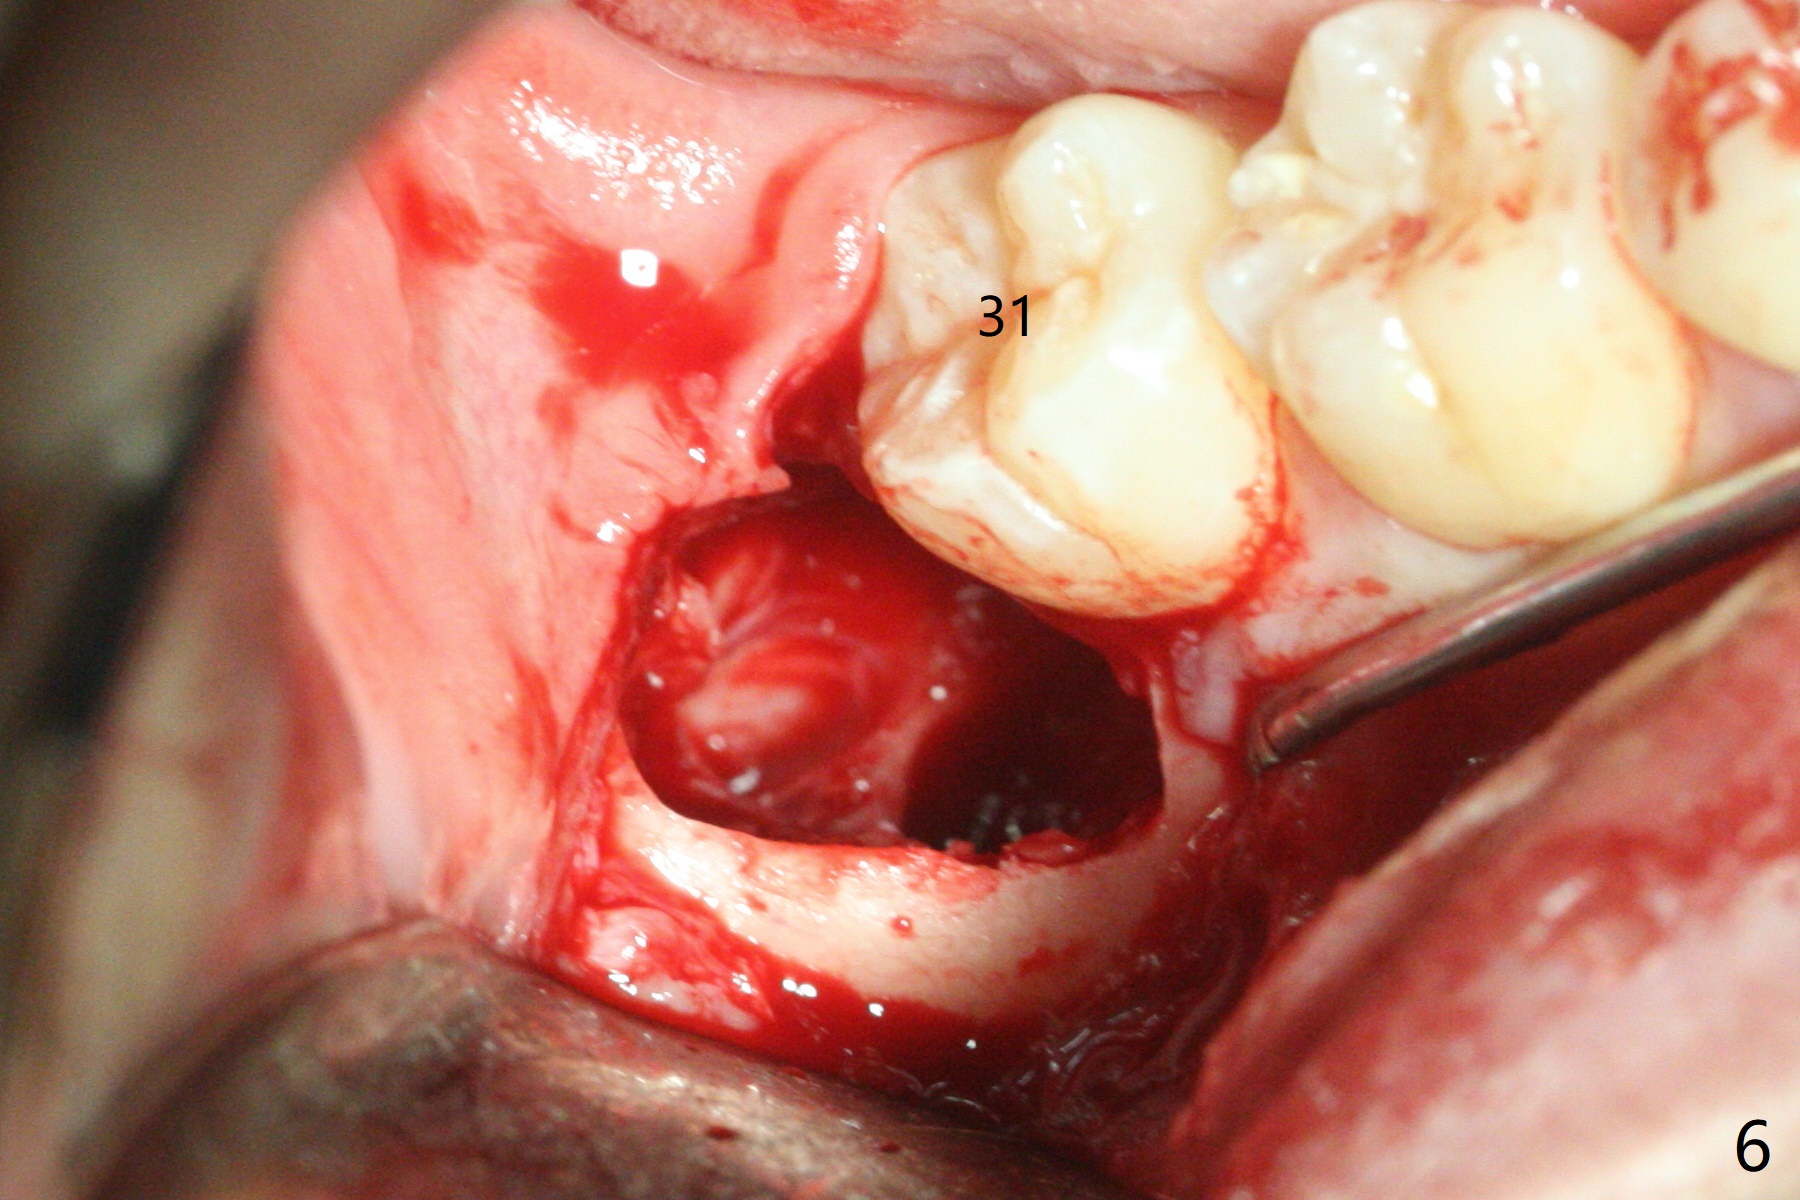

A 19-year-old man returns for #1,16,17 and 32 extraction (Fig.1,2). Because of horizontal impaction of #32 and no bone #31 distal post extraction (Fig.3 *), 3D bond (.5 cc) will be placed in the mesial socket of #32 (Fig.4 red), while Osteogen plug (1/2 (O)) in the distal one. Since there is no bony defect between #17 and 18 after extraction (Fig.5 *), a piece of Osteogen plug (cut half apical) will be inserted in #17 socket, whereas 2 small pieces of Osteogen plug placed in the apical portions (triangle and spindle shaped). Take posterior panoramic X-ray postop (bitewing type, CT format, not XV). There appears bone formation in the socket 5 months postop (Fig.10,11).

Since #32 sockets seem large, extending mesiobuccal (Fig.6), Bond Apatite (1 cc) is placed instead (Fig.7 B), covered by 1/3 of Osteogen plug (O) and sutured with 4-0 PGA. Extraction of #17 is also difficult. As 2 sockets are indistinct, a piece of Osteogen plug with split is placed (Fig.8) upside down (Fig.9 vs. Fig.5). There appears bone formation in the socket 5 months postop (Fig.10,11).